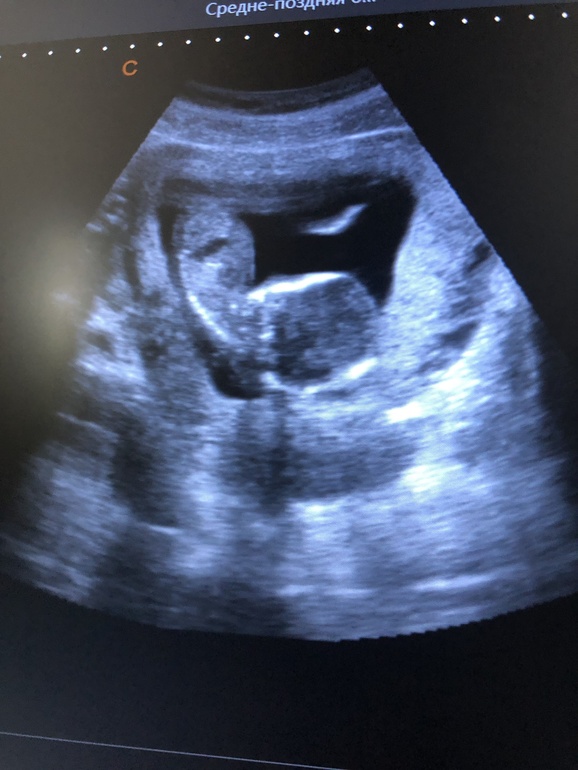

Узи в 14,3 недель))) +фото!

УЗИ, КТГ, доплерМы растём, пока только внутри) снаружи я вовсе не беременная дама. По узи срок ровно 15 недель, весим уже целых 100 грамм! Пол мамке так ни кто и не собирается показывать, характерная мелюзга, видимо, растёт) но, чувствую, что это девочка. Не знаю почему) наверно, уж сильно дочку хочу.

Вот фото положения дитя